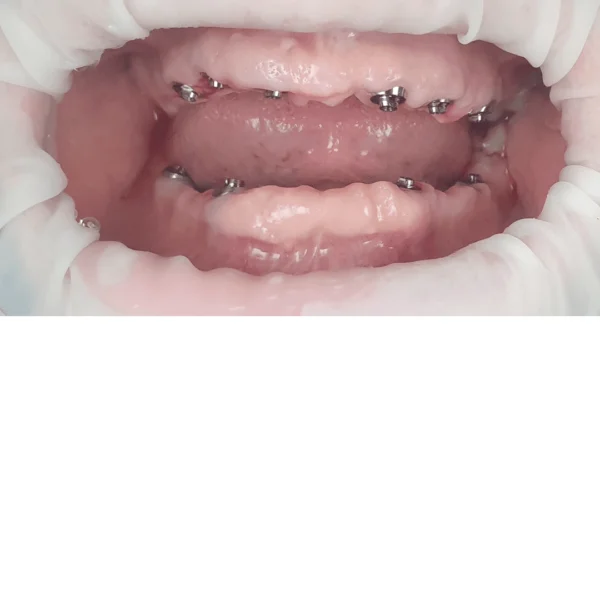

Implantul dentar este adesea recomandat deoarece prezintă foarte multe avantaje, iar, de multe ori, este unica soluție pentru protezarea unei edentații.